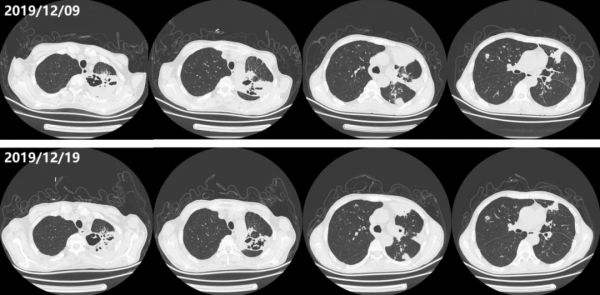

4.影像資料:胸部CT(2019/12/9):右肺上葉可見多髮結節影,部分結節內可見空洞形成,左肺上葉及下葉可見多發斑片狀及大片狀高密度影,部分病灶內可見充氣支氣管徵及空洞形成(圖1)。心臟、腹部及血管超聲未見明顯異常。

經治療,患者體溫逐漸降至正常,感染指標下降(圖2),12月19日複查胸部CT提示肺部病灶較2019年12月9日有所吸收(圖1)。12月20日停用伏立康唑,亞胺培南西司他丁降級,12月24日出院。